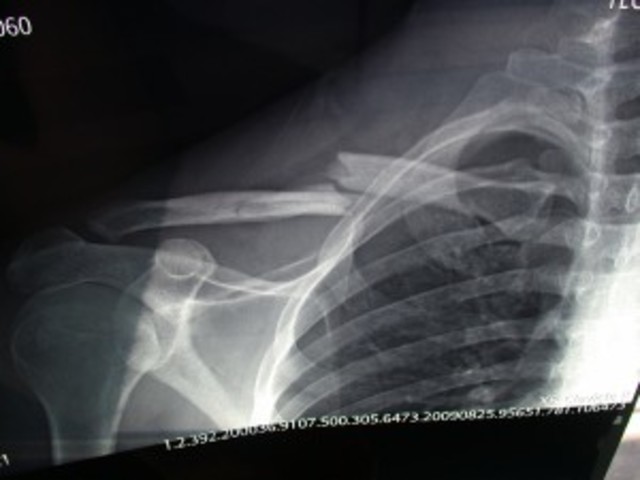

• Broke my collar bone

Broke my collar bone

me caí de mi monopatín

me rompí mi collar bone

fuí a la hospital